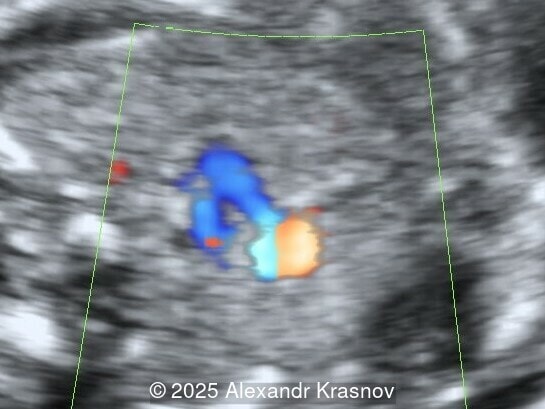

Image 3

Our ultrasound showed biometry data corresponding to 21 weeks of gestation. During echocardiography, an abnormal drainage of the pulmonary veins was detected in which the pulmonary veins drain into a venous collector linked to the superior vena cava. The four-chamber view and the three-vessel view were altered and raised suspicion of a pathology. The grayscale and color Doppler images of the four-chamber view indicate a smooth posterior wall of the left atrium, increased distance between the left atrium and the descending aorta and the absence of pulmonary veins entering the left atrium (Image 1, 2; Video 1, 2). In the three-vessel view, the diameter of the superior vena cava appears larger than that of the aorta (Image 3, Video 3). In the images of the venae cava, a significant difference is seen between the diameters of the inferior and superior vena cava with significant enlargement of the superior vena cava (Image 4, Video 4). Additionally, there is a pulmonary venous confluent chamber (“twig sign”) behind the left atrium (Image and Video 5). A vertical ascending vein connects the confluent chamber with the superior vena cava where it drains blood from the pulmonary veins (Images 6, 7; Video 6).